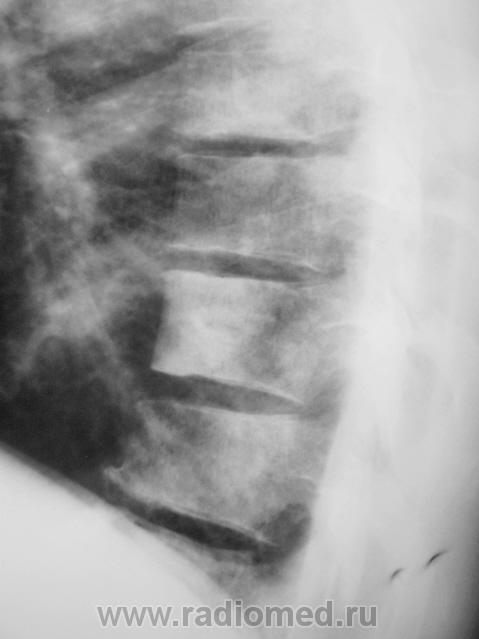

Пациент взят на контроль после проведения профилактической флюорографии.

Возможно остеопойкилия? Рекомендовала бы рентгенографию периферических отделов скелета (кисти, голеностопы...)

а в легких изменения?очаговые тени в легких и склеротические изменения тела толкают на мысли о метастатическом поражении.

Мы тоже высказали мнение о наличии метастазов. У пациента установлен ( в области) рак предстательной железы, диагноз в ООД вверифицирован.